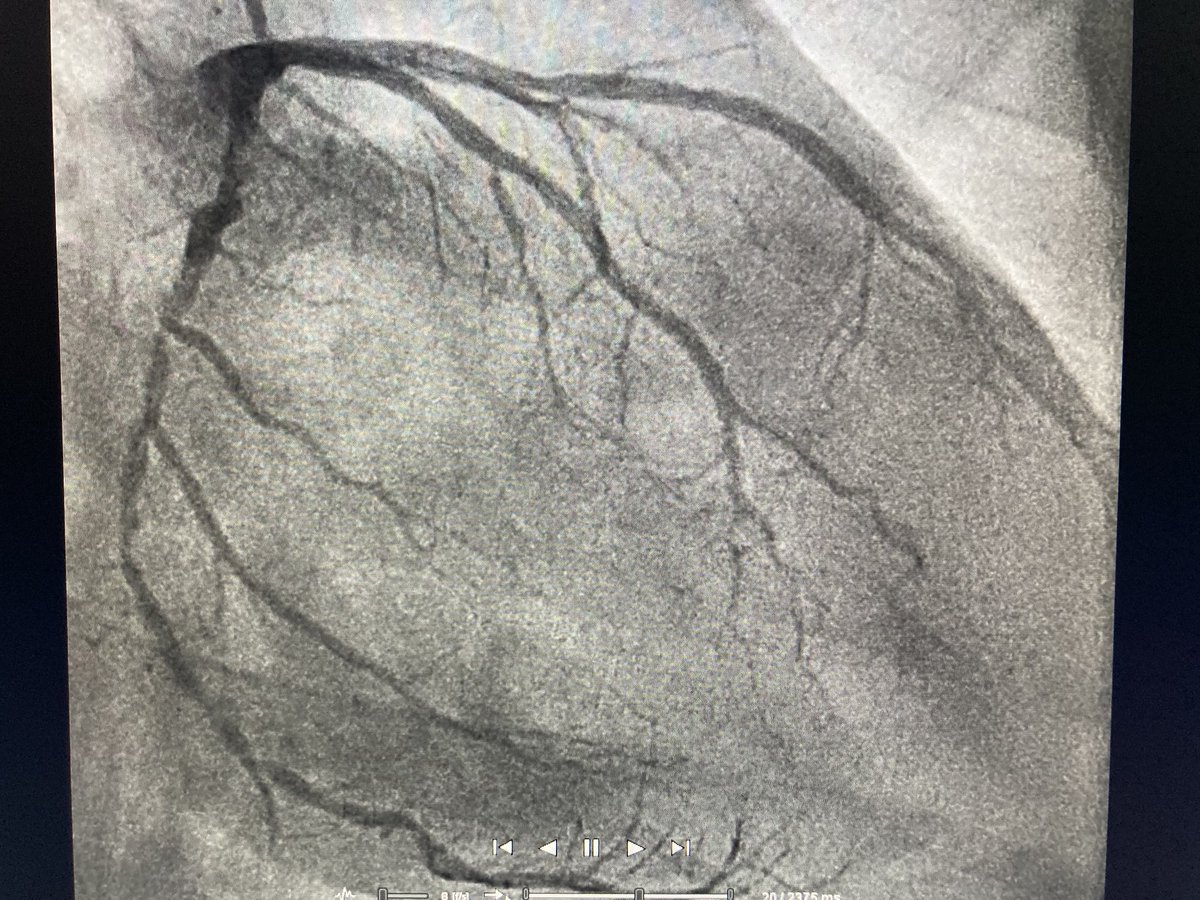

How is it that sometimes one vessel (here: Cx) seems totally destroyed by CAD while others (RIM, LAD) only have mild disease? Smoking, lipids etc should affect all vessels the same way, right? Anybody understand the underlying pathological process?